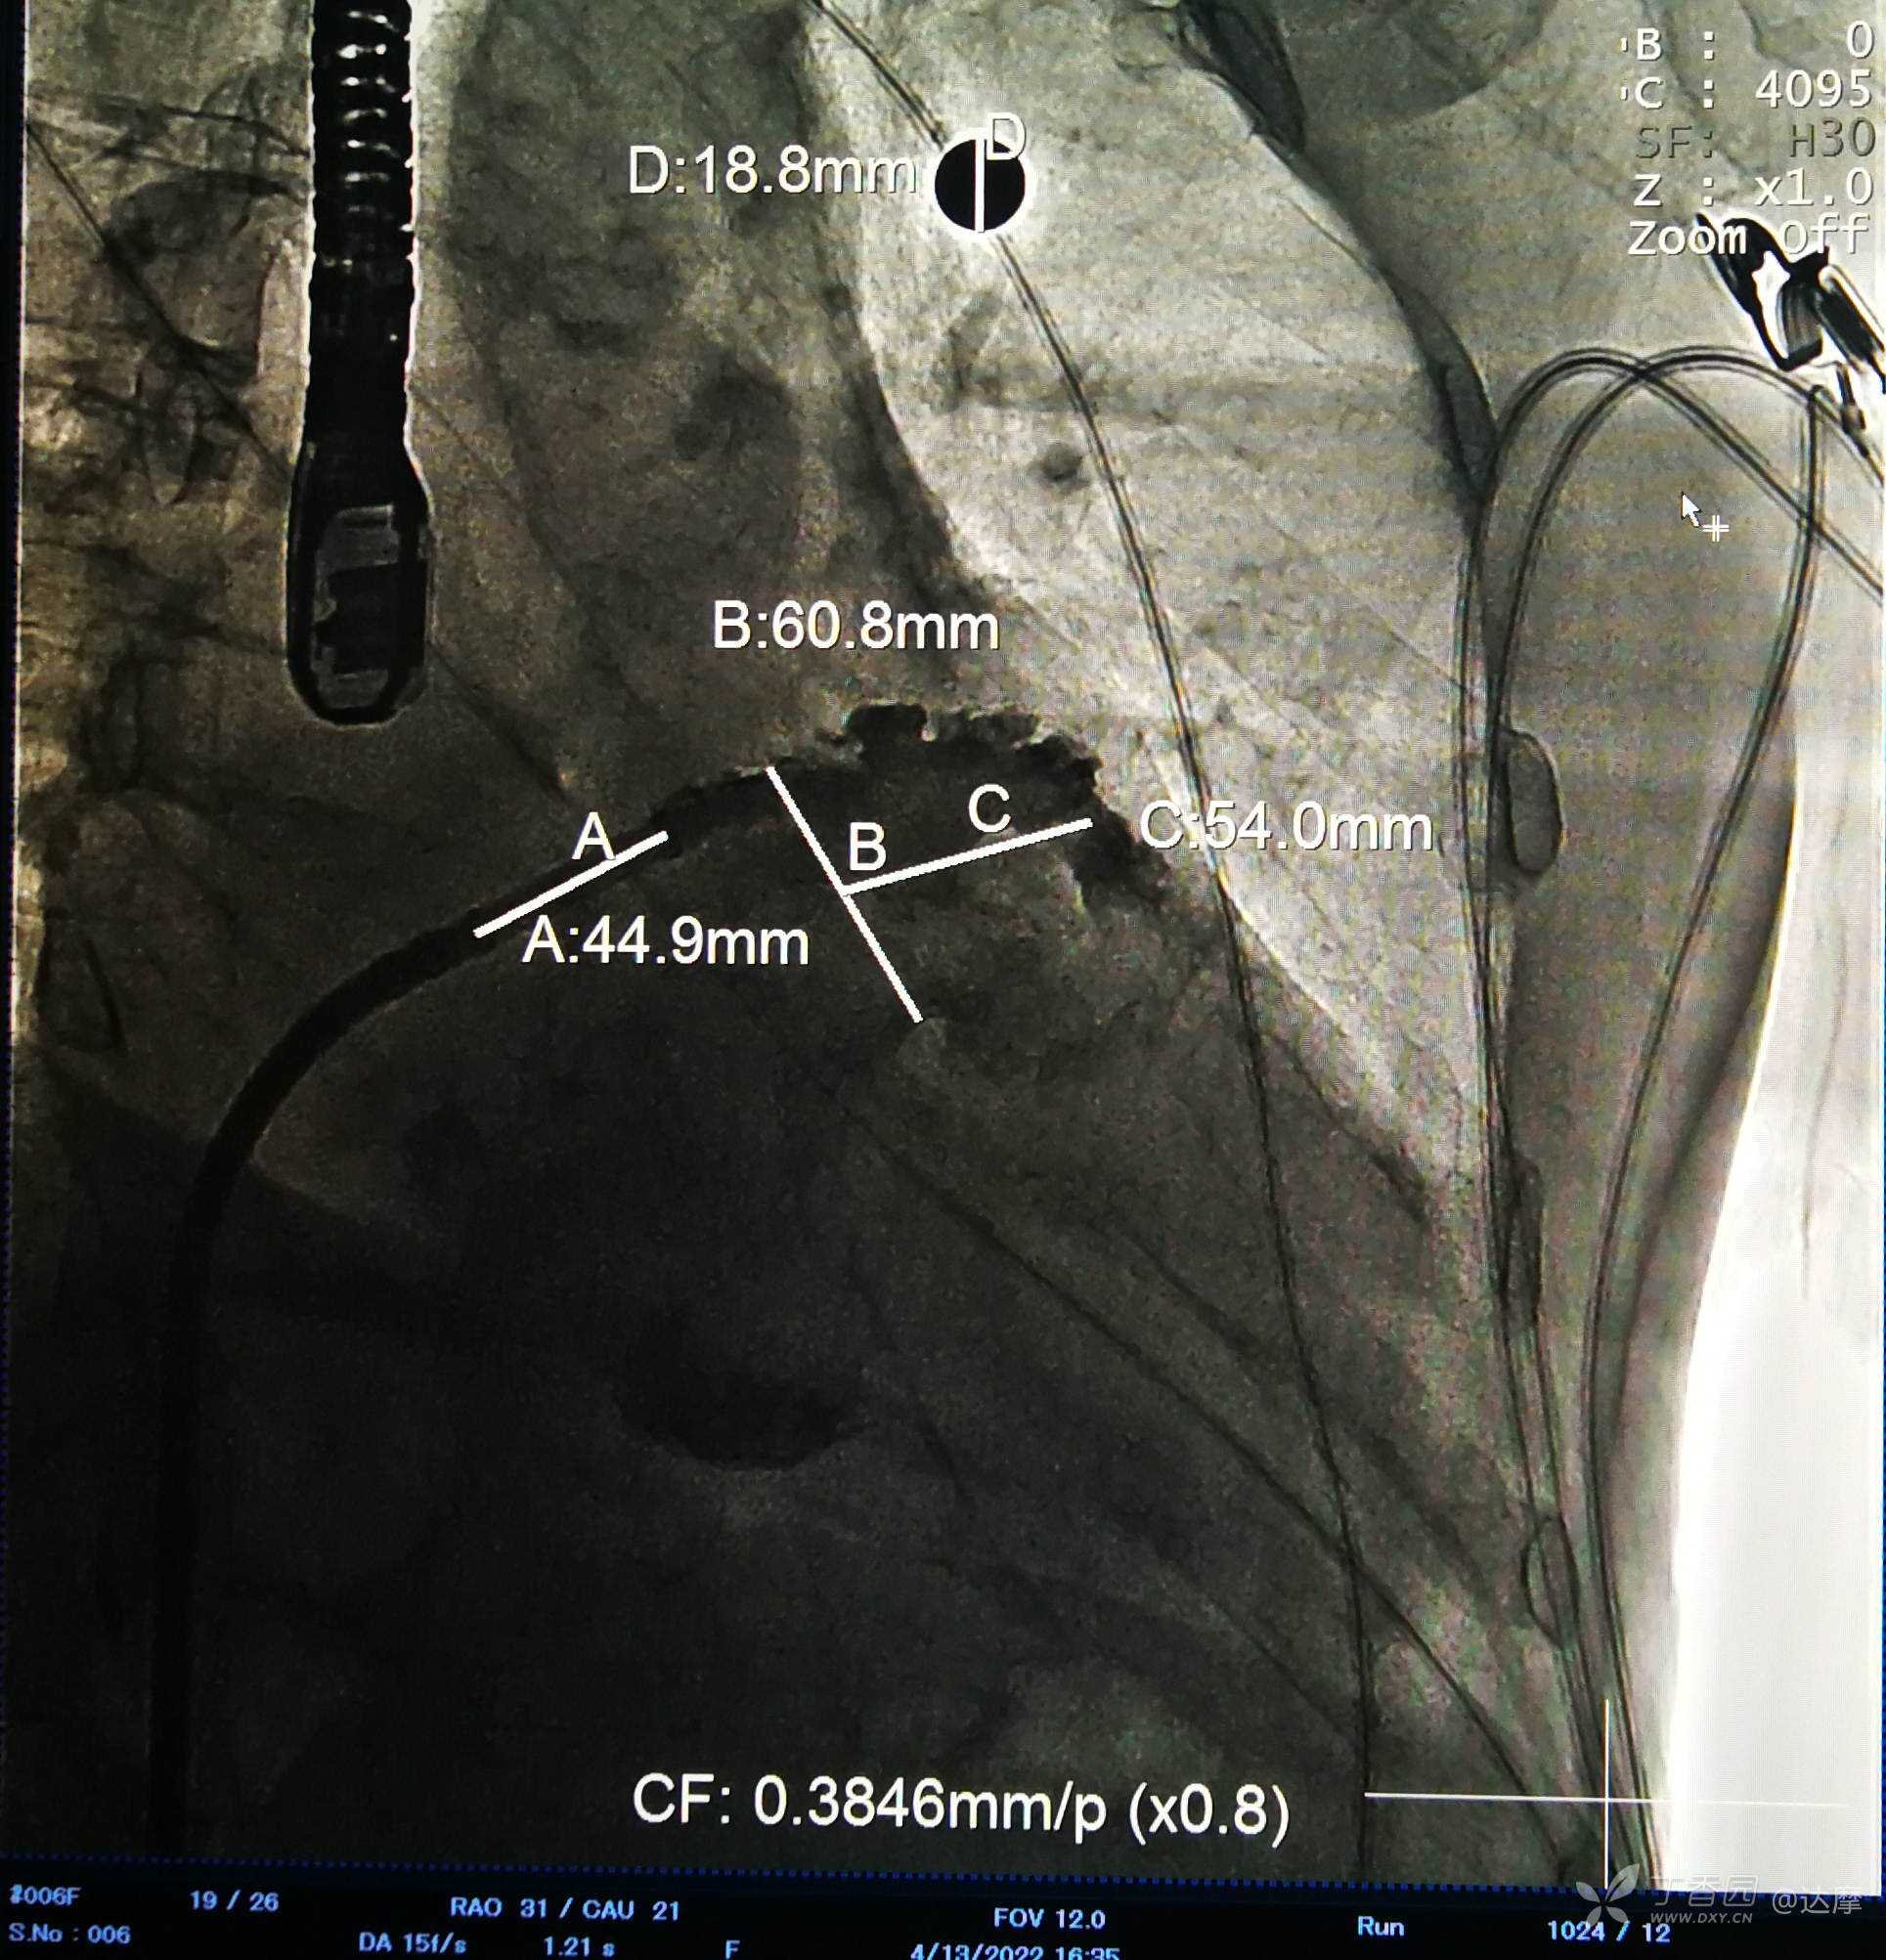

左心耳造影如下:

测量数据如下: